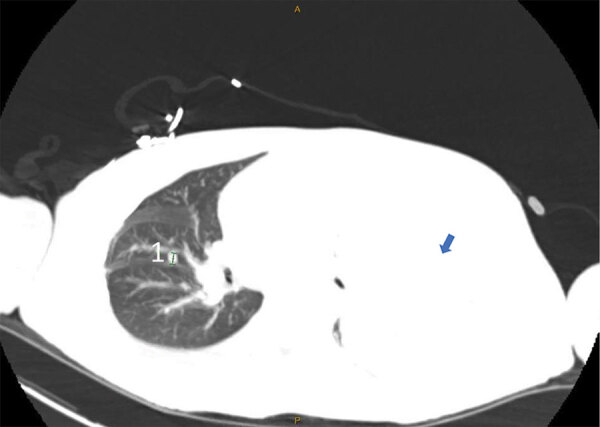

Description:A 33-year-old man in Baltimore, Maryland, USA, with untreated HIV infection had a 74-day course of mpox with multiorgan system involvement and unique clinical findings. In this clinical experience combining 3 novel therapeutic regimens, this patient died from severe mpox in the context of untreated HIV and advanced immunodeficiency.